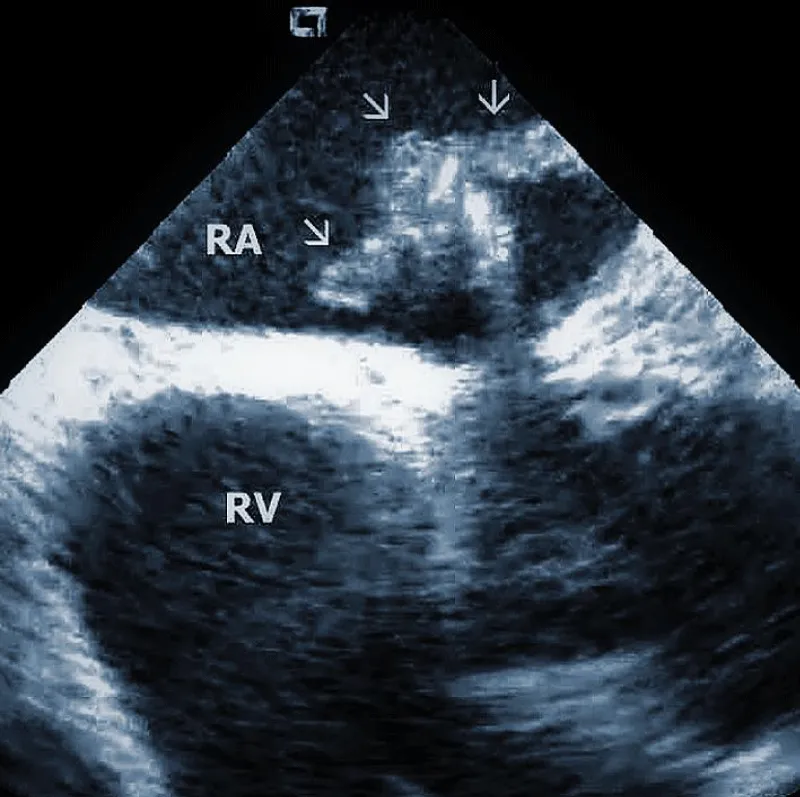

Figure 1B: ICD lead crossing the tricuspid valve between the right atrium (RA) and right ventricle (RV). Arrows mark lead adherent echodensities. The ICE catheter is positioned in the RA.

From the right atrial position, the course of the lead (or leads) could be overlooked. This is the best view to observe the presence of tricuspid regurgitation and the existence and location of lead adherent echo densities (LAE). Positioning the catheter in the superior vena cava or higher enables assessment of the lead attachments or binding sites in this region. Subtotal or total vein occlusion could be detected at the same time.